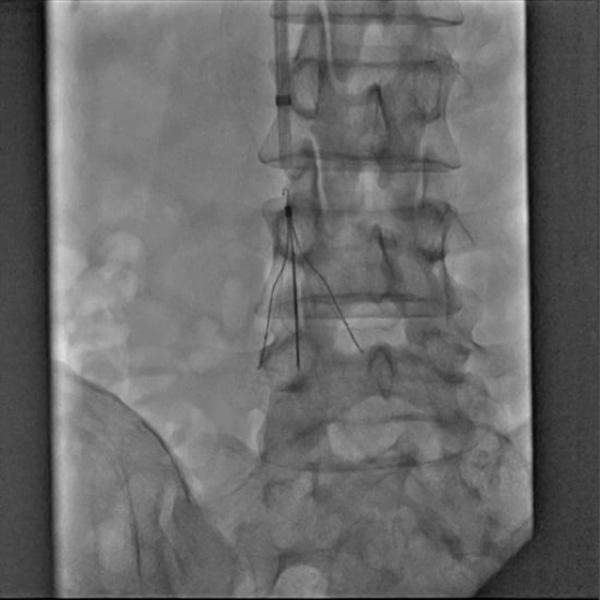

下大静脈フィルターのイメージ

さまざまな理由で抗凝固療法を行えないときは、下大静脈フィルターをお腹の静脈に留置して、肺に血栓が行かないようにします。